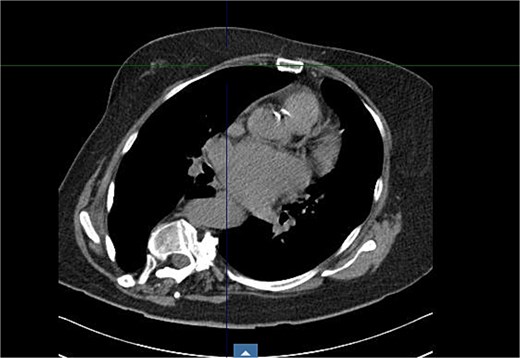

The patient’s comorbidities were extensive and included: heart failure with preserved ejection fraction (HFpEF), atrial fibrillation, left atrial enlargement, Barrett’s esophagus, hypertension, hypercholesterolemia, multiple benign hepatic cysts, osteoporosis, a large sliding hiatal hernia containing the gastric fundus and celiac artery, and descending thoracic aortic tortuosity causing chronic left lower lobe segmental atelectasis (Fig. 2).

Coronal CT showing curvature of the thoracic aorta tortuosity compressing the distal esophagus and causing chronic left lower lobe segmental atelectasis.